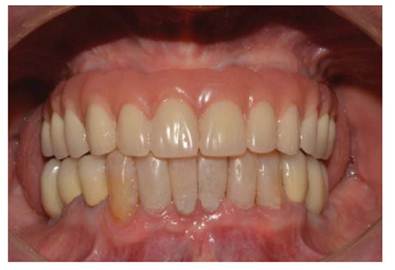

Luego se procedió a la fabricación de la estructura metálica del maxilar superior con la ayuda de una pantalla de silicona obtenida del protocolo reverso, esta estructura presentó un asentamiento pasivo comprobado clínica y radiográficamente luego de realizar los cortes y soldajes necesarios (Figura 5). Se realizó el enfilado para la prótesis híbrida con dientes Ivostar/Gnathostar donde se evaluó estética y fonación. En el maxilar inferior se torquearon los pilares CM recto para la pieza 35 y Pilares angulados (17°) a nivel de piezas 36 y 46 fresados con la ayuda de una guía de colocación de pilares (Figura 6) y se fabricaron coronas de metal cerámica. Para finalizar se procede a la instalación de la prótesis híbrida superior, la cementación de las coronas con cemento temporal y la instalación de una férula de DCM (figura a y b). Finalizado el tratamiento se realizaron controles periodontales y protésicos periódicos donde se comprobó la correcta concientización del paciente en cuanto a su mantenimiento. (Figura 8)

Figura 7 a Instalación de la prótesis híbrida superior

Figura 7 b coronas cementadas sobre implantes en Max. Inferior